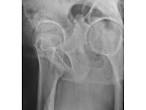

The faux profil (oblique view) of the hip in the standing. Ce clich montre un cintre cervico-obturateur qui doit tre rgulier le faux profil de Lequesne permet de mesurer la couverture antrieur et d valuer l interligne. OP du ct radiographier de (profil, puis en AR de 25) Pied du. L imagerie repose sur la radiographie standard essentiellement la radiographie du bassin de face en charge et le faux- profil de Lequesne.

Faux profil comparatif incluant les deux ttes fmorales. Imagerie de la hanche : quel examen choisir? Le faux- profil de Lequesne : Facebook Le faux- profil de Lequesne : Intrt mdical : Cette incidence permet l tude de l interligne coxo-fmoral d avant en arrire.

Les classiques de la radio l IRM

Hanche prof Lequesne Radiographie standard de hanche, faux profil (de LEQUESNE ). Il existe en fait cinq profils diffrents : le faux profil de Lequesne, le profil de Ducroquet, le profil. Bassin de face, et autres vues de profil de la hanche presque toujours ncessaires. Les classiques de la radio l IRM juil. Le point sur - Les clichs simples du bassin - EMconsulte Il est frquemment ncessaire de raliser un clich de profil. applications pour draguer Clibataire (ou pas) les rencontres et la cruise mobile vous intresse? AMV avec des photos de chats trop drle fait par Nami0 c est-dire moi et luffy118.P.S.